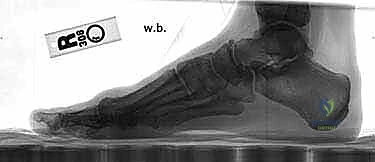

Effective preoperative planning is the cornerstone of a successful outcome. We evaluate a series of weight-bearing radiographs: AP and lateral views of the foot.

- Radiographic Analysis:

- Metatarsal Length: We assess the relative lengths of the metatarsals. Significant shortening of the first metatarsal can lead to transfer metatarsalgia postoperatively. While this osteotomy typically results in minimal shortening (average 0.98 mm), it's a factor to consider.

- Intermetatarsal Angle (IMA) and Hallux Valgus Angle (HVA): These are our primary measurements to quantify the deformity and guide the osteotomy's magnitude.

- Joint Congruency: We look for any subluxation or incongruity of the first MTP joint.

- Medial Eminence Size: This dictates the extent of our bunionectomy.

- Sesamoid Position: We note the lateral displacement of the sesamoids, which should ideally reduce with successful correction.

- Templating the Osteotomy: We routinely mark the proposed osteotomy directly on the radiograph. This allows us to visualize the wedge to be resected, its apex location, and the desired amount of correction. This mental rehearsal is invaluable.